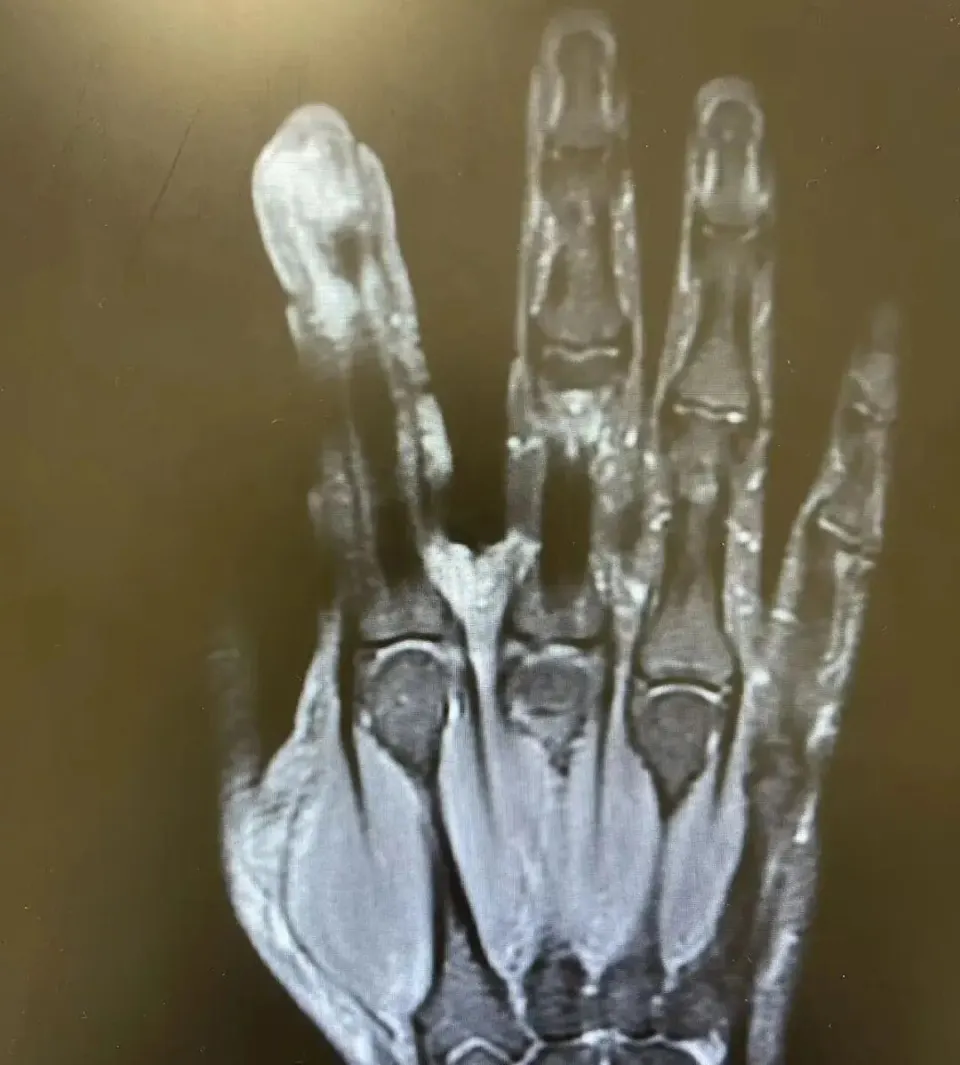

经过一系列检查,李大哥破溃的左手指尖严重感染,厌氧消化链球菌顺着破损处钻到骨头里,引发了严重骨髓炎,“再晚一步,就会有截肢风险!”卢荟建议李大哥必须先手术清创再配合抗感染治疗才能脱险。因为随着骨髓炎细菌入血,还会出现感染性休克的致命风险!

手术室里,卢荟帮李大哥“刮掉”坏死的骨头碎片,清除坏死的肌肉与皮肤。

经过专家团队的精心救治,李大哥的手指保住了,但因感染已经严重破坏了他的关节,手指末节的活动今后会存在一定的受限,很难恢复如原来那般灵巧。